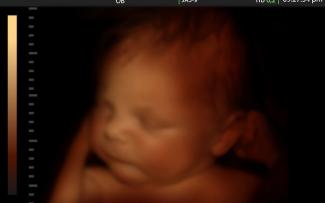

Všetky boli údajne zo zdravotných a naliehavých dôvodov, čo je jediný dôvod, prečo sú interrupcie v Texase legálne. Údaje zachytávajú len obyvateľov Texasu. Odborníci však potvrdzujú, že interrupcia nie je z lekárskeho hľadiska nevyhnutná za žiadnych okolností, a zástancovia života poukazujú na to, že ide vždy o morálne neprípustné, úmyselné zabitie nevinnej ľudskej bytosti.

Akkoľvek je pokles celkového množstva potratov krokom k úplnému odstráneniu potratov, štatistiky nemusia vykresľovať úplný obraz kvôli dostupnosti chemických potratových liekov a stále ukazujú, že bolo zabitých 22 nenarodených detí.